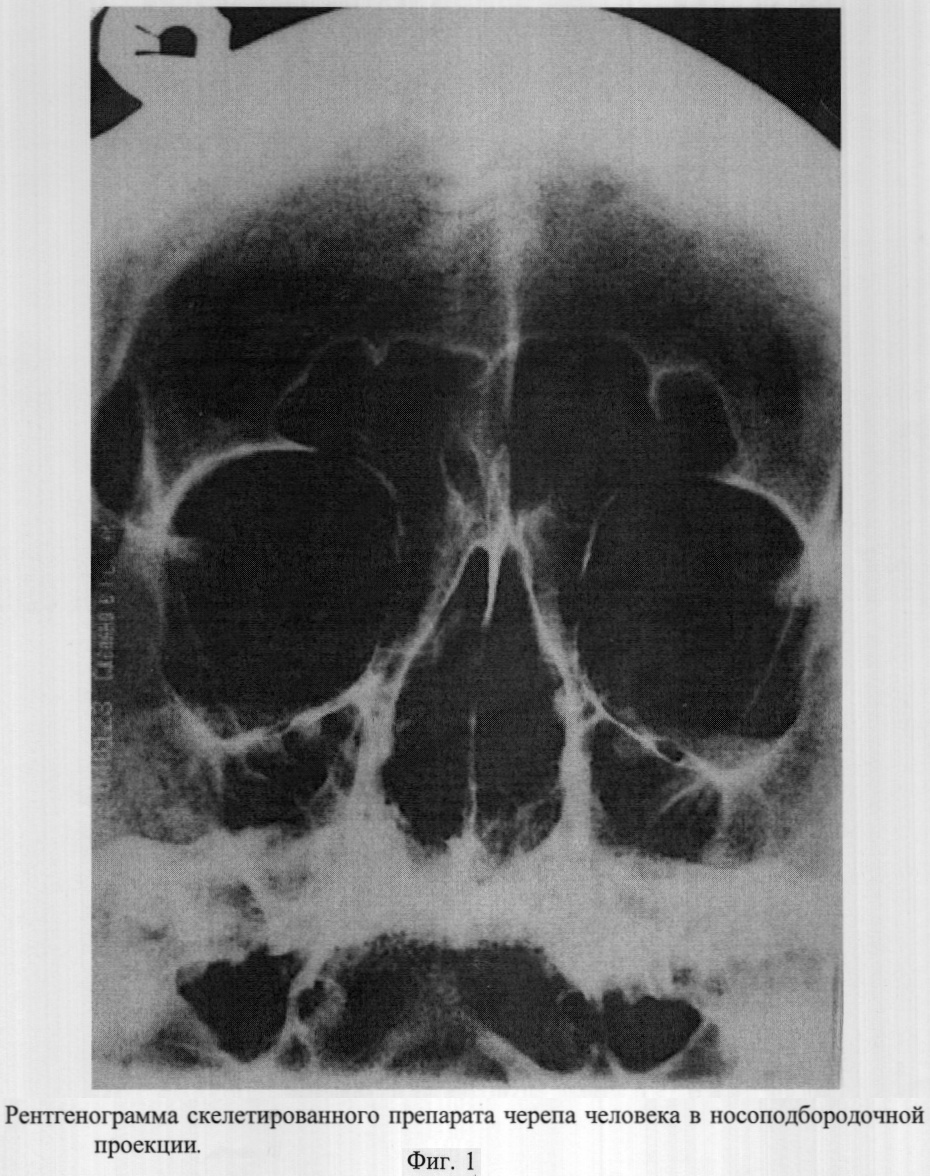

Рентгенография придаточных пазух в носоподбородочной проекции в вертикальном положении больного чаще всего используется для диагностики патологических процессов этой анатомической области (Кишковский А.Н., Тютин Л.А., Есиновская Г.Н. Атлас укладок при рентгенологических исследованиях. – Л.: Медицина. 1987. – 520 с.).

Рентгенография в данной проекции осуществляется следующим образом: больного усаживают у стойки с подвижной отсеивающей решеткой, устанавливая голову таким образом, чтобы подбородок и кончик носа касались панели стойки. Голова устанавливается строго симметрично; срединная сагиттальная плоскость перпендикулярна плоскости стойки и соответствует средней линии деки, рентгеновский луч перпендикулярен кассете и деке.

– проекционное наслоение пирамид височных костей на нижние отделы верхнечелюстных пазух, делающее недоступным для визуализации альвеолярные бухты (фиг.1);

– разнообразие ошибок в интерпретации рентгенологических данных, обусловленных значительной вариабельностью строения верхнечелюстных и лобных пазух (асимметрии формы и объема пазух, варианты бухт и т.д.);

– необходимость производства нескольких снимков в других укладках или выполнения дополнительных лучевых исследований для получения полной информации о состоянии околоносовых пазух передней группы.